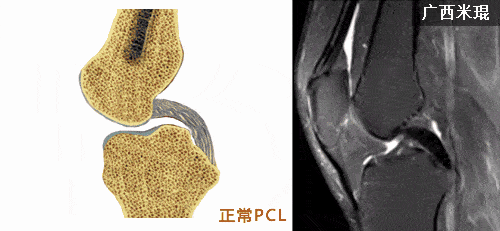

后交叉韧带(pcl)

交叉韧带解剖及损伤的mri诊断

后交叉韧带(pcl)损伤的mri诊断